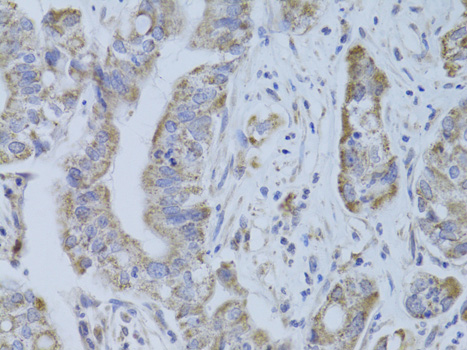

ApplicationWB, IHC, IF, IP